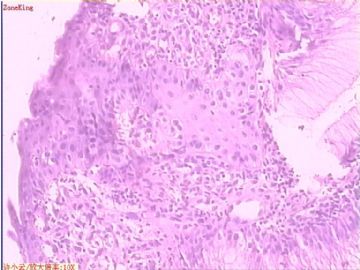

贲门息肉?

姓    名: ××× 性别:  女 年龄:  53

简要病史:  胃镜见,食道下段齿状线上可见一圆形隆起,有蒂,表面光滑,大小0.5X0.5X0.3cm.

各位老师,胃粘膜处出现的鳞状上皮有问题么?

• 贲门息肉?图3

图3

可能是炎症刺激所致,不敢报恶性。

鳞状上皮没大问题,可能受炎症影响,稍有增生.

没有发现恶性证据,小心点儿可以拖个尾巴,譬如伴轻度异型增生。

本帖最后由 于 2009-11-21 09:51:00 编辑   谢谢各位老师指点,最终诊断为:贲门慢性炎症,伴局灶细胞轻度异型增生。